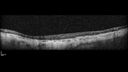

87 year old female. Severe macular bleed 15 years ago OD. Now with disciform scar. Left eye has progressing geographic atrophy. VA OD: HM, OS: 5/200. IOP normal OU